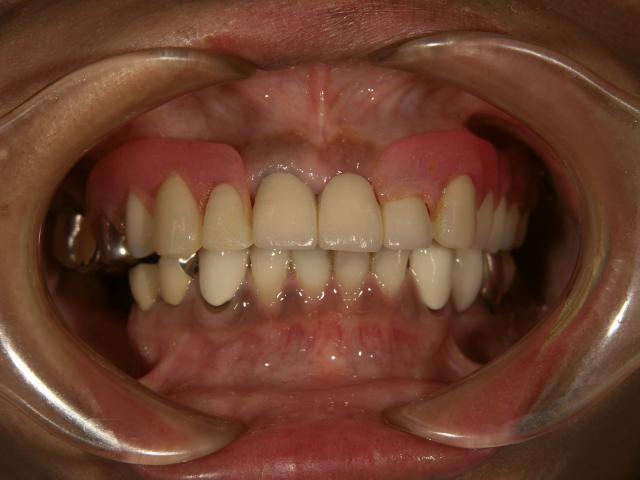

テレスコープタイプの入れ歯(上顎)

2007/04/27

70代女性 担当:院長

義歯が磨り減ってよく噛めない。

唇を噛んでしまう。

前歯の部分が見えないので、自然に見えるようにして欲しい。

術前space術後

術前 術後

1年ほどかけて咬合を挙げてから新義歯作成しました。

新義歯作成 新義歯作成

術後の自然観比較してください!